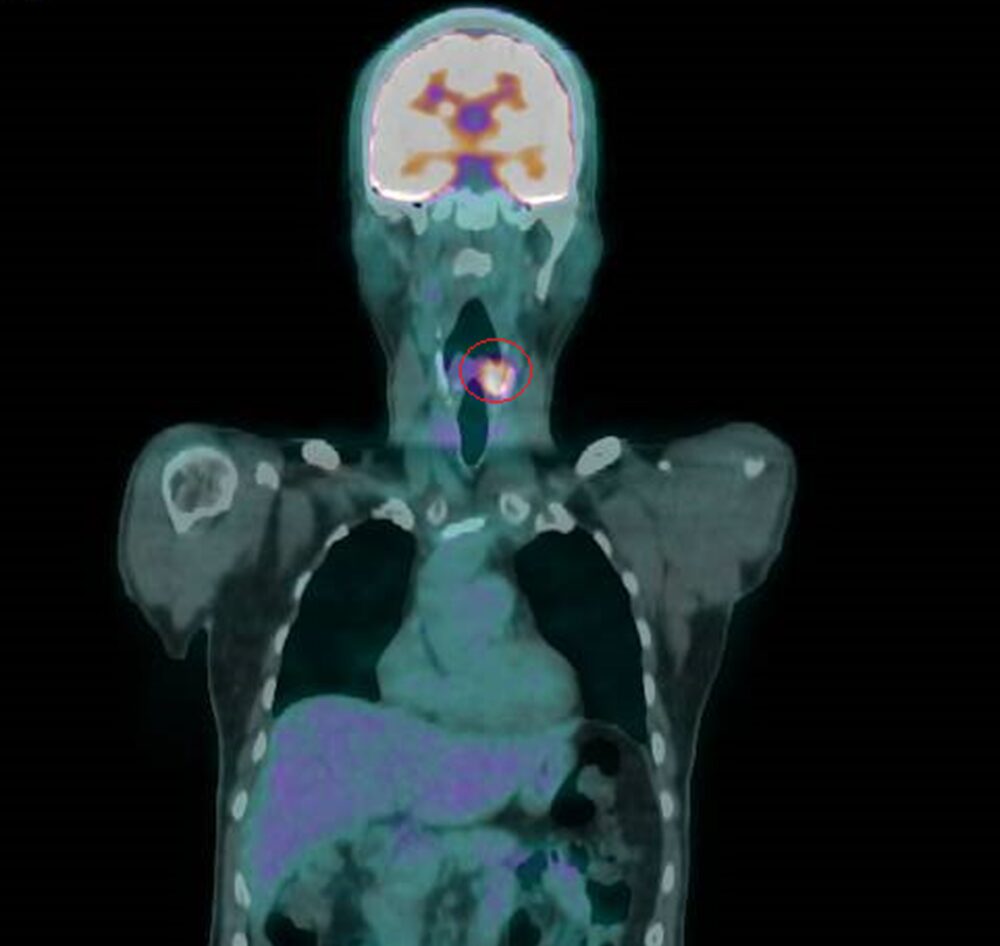

衛福部彰化醫院耳鼻喉科主任許嘉方表示,曾先生3年前喉嚨疼痛不癒,經內視鏡、電腦斷層等檢查發現,其左下咽處有個2公分的腫瘤,切片確定為惡性,是第2期癌症,不進行切除手術,採放射及化學療法,治療後腫瘤消失。

▲電腦斷層等檢查發現,其左下咽處有個2公分的腫瘤。(圖/彰化醫院提供)